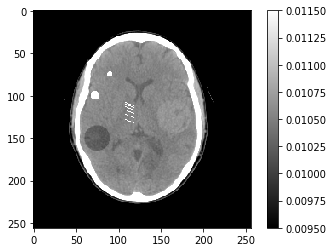

Partie 2 - Non-idéalités du détecteur

Un détecteur présente plusieurs non idéalités ; en premier lieu, il présente des dérives en gains et en offsets. Cela signifie que la mesure faite au niveau d’une cellule du détecteur (un pixel d’un détecteur plan, ou un bin d’un détecteur linéaire), au lieu de mesurer l’intensité $I$ des photons X qui arrivent à la cellule, on mesure \(I_c = \alpha I + \beta.\) $\alpha$ est un gain (proche de 1 généralement), et $\beta$ est un offset. Si on ne fait pas attention à $\alpha$ et $\beta$, on se retrouve avec une projection corrompue $p_c = \log(I_0)-\log(I_c)$.

Chargez l’image ci-dessous, et regardez son sinogramme :

5

scale = 1e-5

img = np.fromfile('CTscan.raw',dtype='float32').reshape((256,256))*scale

ctDisplay = {'vmin':950*scale,'vmax':1150*scale}

plt.imshow(img,**ctDisplay)

plt.colorbar()

1

<matplotlib.colorbar.Colorbar at 0x7fce56e10fd0>